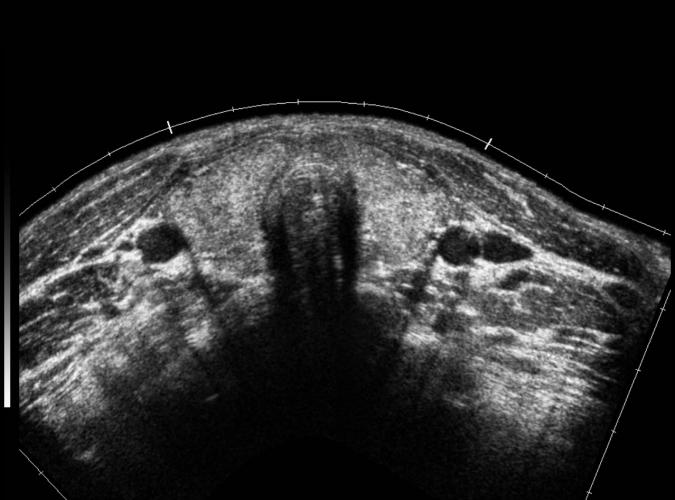

Trans bägge thyroidealoberna samt isthmus.

"Klassisk Hashimotothyroidit" samma pt.som 9k